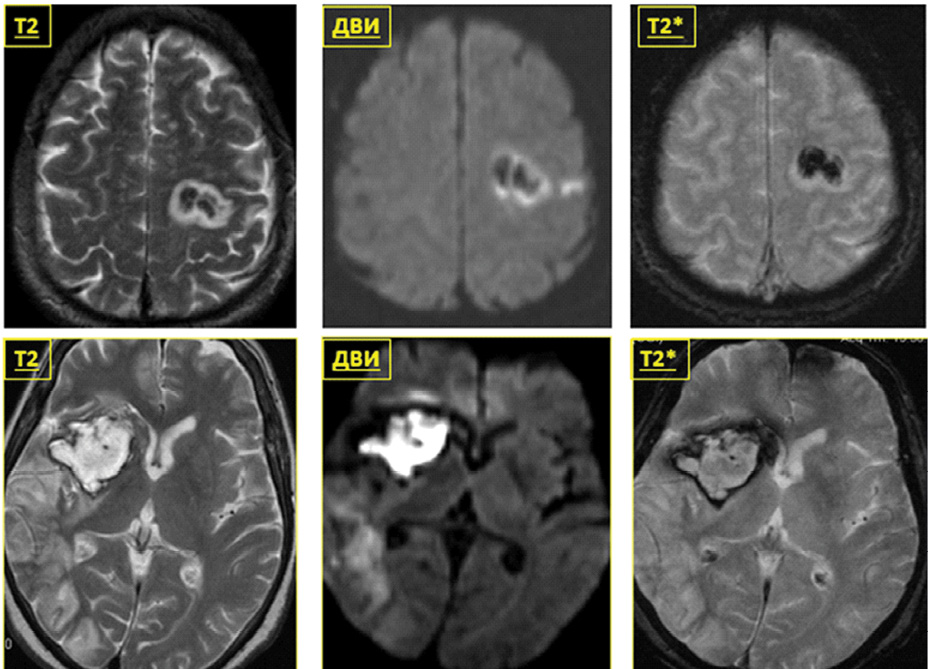

Рисунок 2. ДВИ в определении давности внутримозговой гематомы. А. Внутримозговая гематома в левом полушарии ГМ. Подострый период, 5-й день. Б. Внутримозговая гематома в правом полушарии ГМ. Хронический период, 28-й день.

Figure 2. DWI in determining the time of intracerebral hematoma. А. Intracerebral hematoma in the left hemisphere of the brain. Subacute period, day 5. B. Intracerebral hematoma in the right hemisphere of the brain. Chronic period, day 28.

ДВИ в МРТ часто применяется для определения давности внутричерепных, внутримозговых гематом и контузионных очагов (рисунок 2).

Одной из важнейших задач в оценке состояния пациентов с ЧМТ является определение зон цитотоксического отека как проявления вторичной ишемии. Для этой цели эффективно применяются диффузионно-взвешенные изображения (ДВИ), возникающие за счет движения протонов в тканях ГМ. ДВИ и ADC-карты применяются для дифференциальной диагностики цитотоксического и вазогенного отека вследствие травмы ГМ или ишемии.

Снижение коэффициента диффузии говорит о наличии цитотоксического отека, а увеличение – о развитии вазогенного отека. Особая роль ДВИ отводится в выявлении инфарктов и ДАП [12].